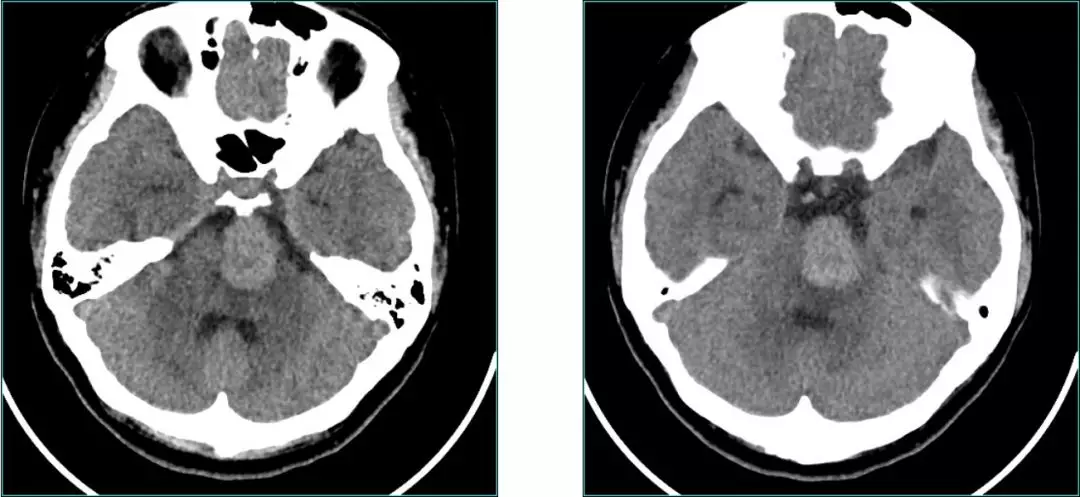

Pre-op CT scan

Pre-op CT Contrast

Post-op CT